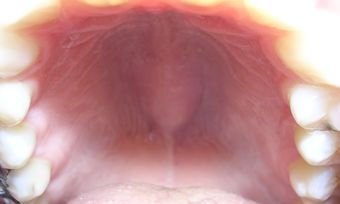

Palate exhibiting torus palatinus.  | |

الحنك (بالإنجليزية: palate)هو التركيب الفاصل بين جوف الأنف وجوف الفم فهو سقف الفم وأرضية الأنف. يمتد الحنك نحو الخلف ليفصل جزئياً بين البلعوم الأنفي والبلعوم الفموي. للحنك شكل القبة وهو يتألف من قسمين هما الحنك الصلب الذي يشكل الجزء الأمامي والحنك الرخو الذي يشكل الجزء الخلفي منه.